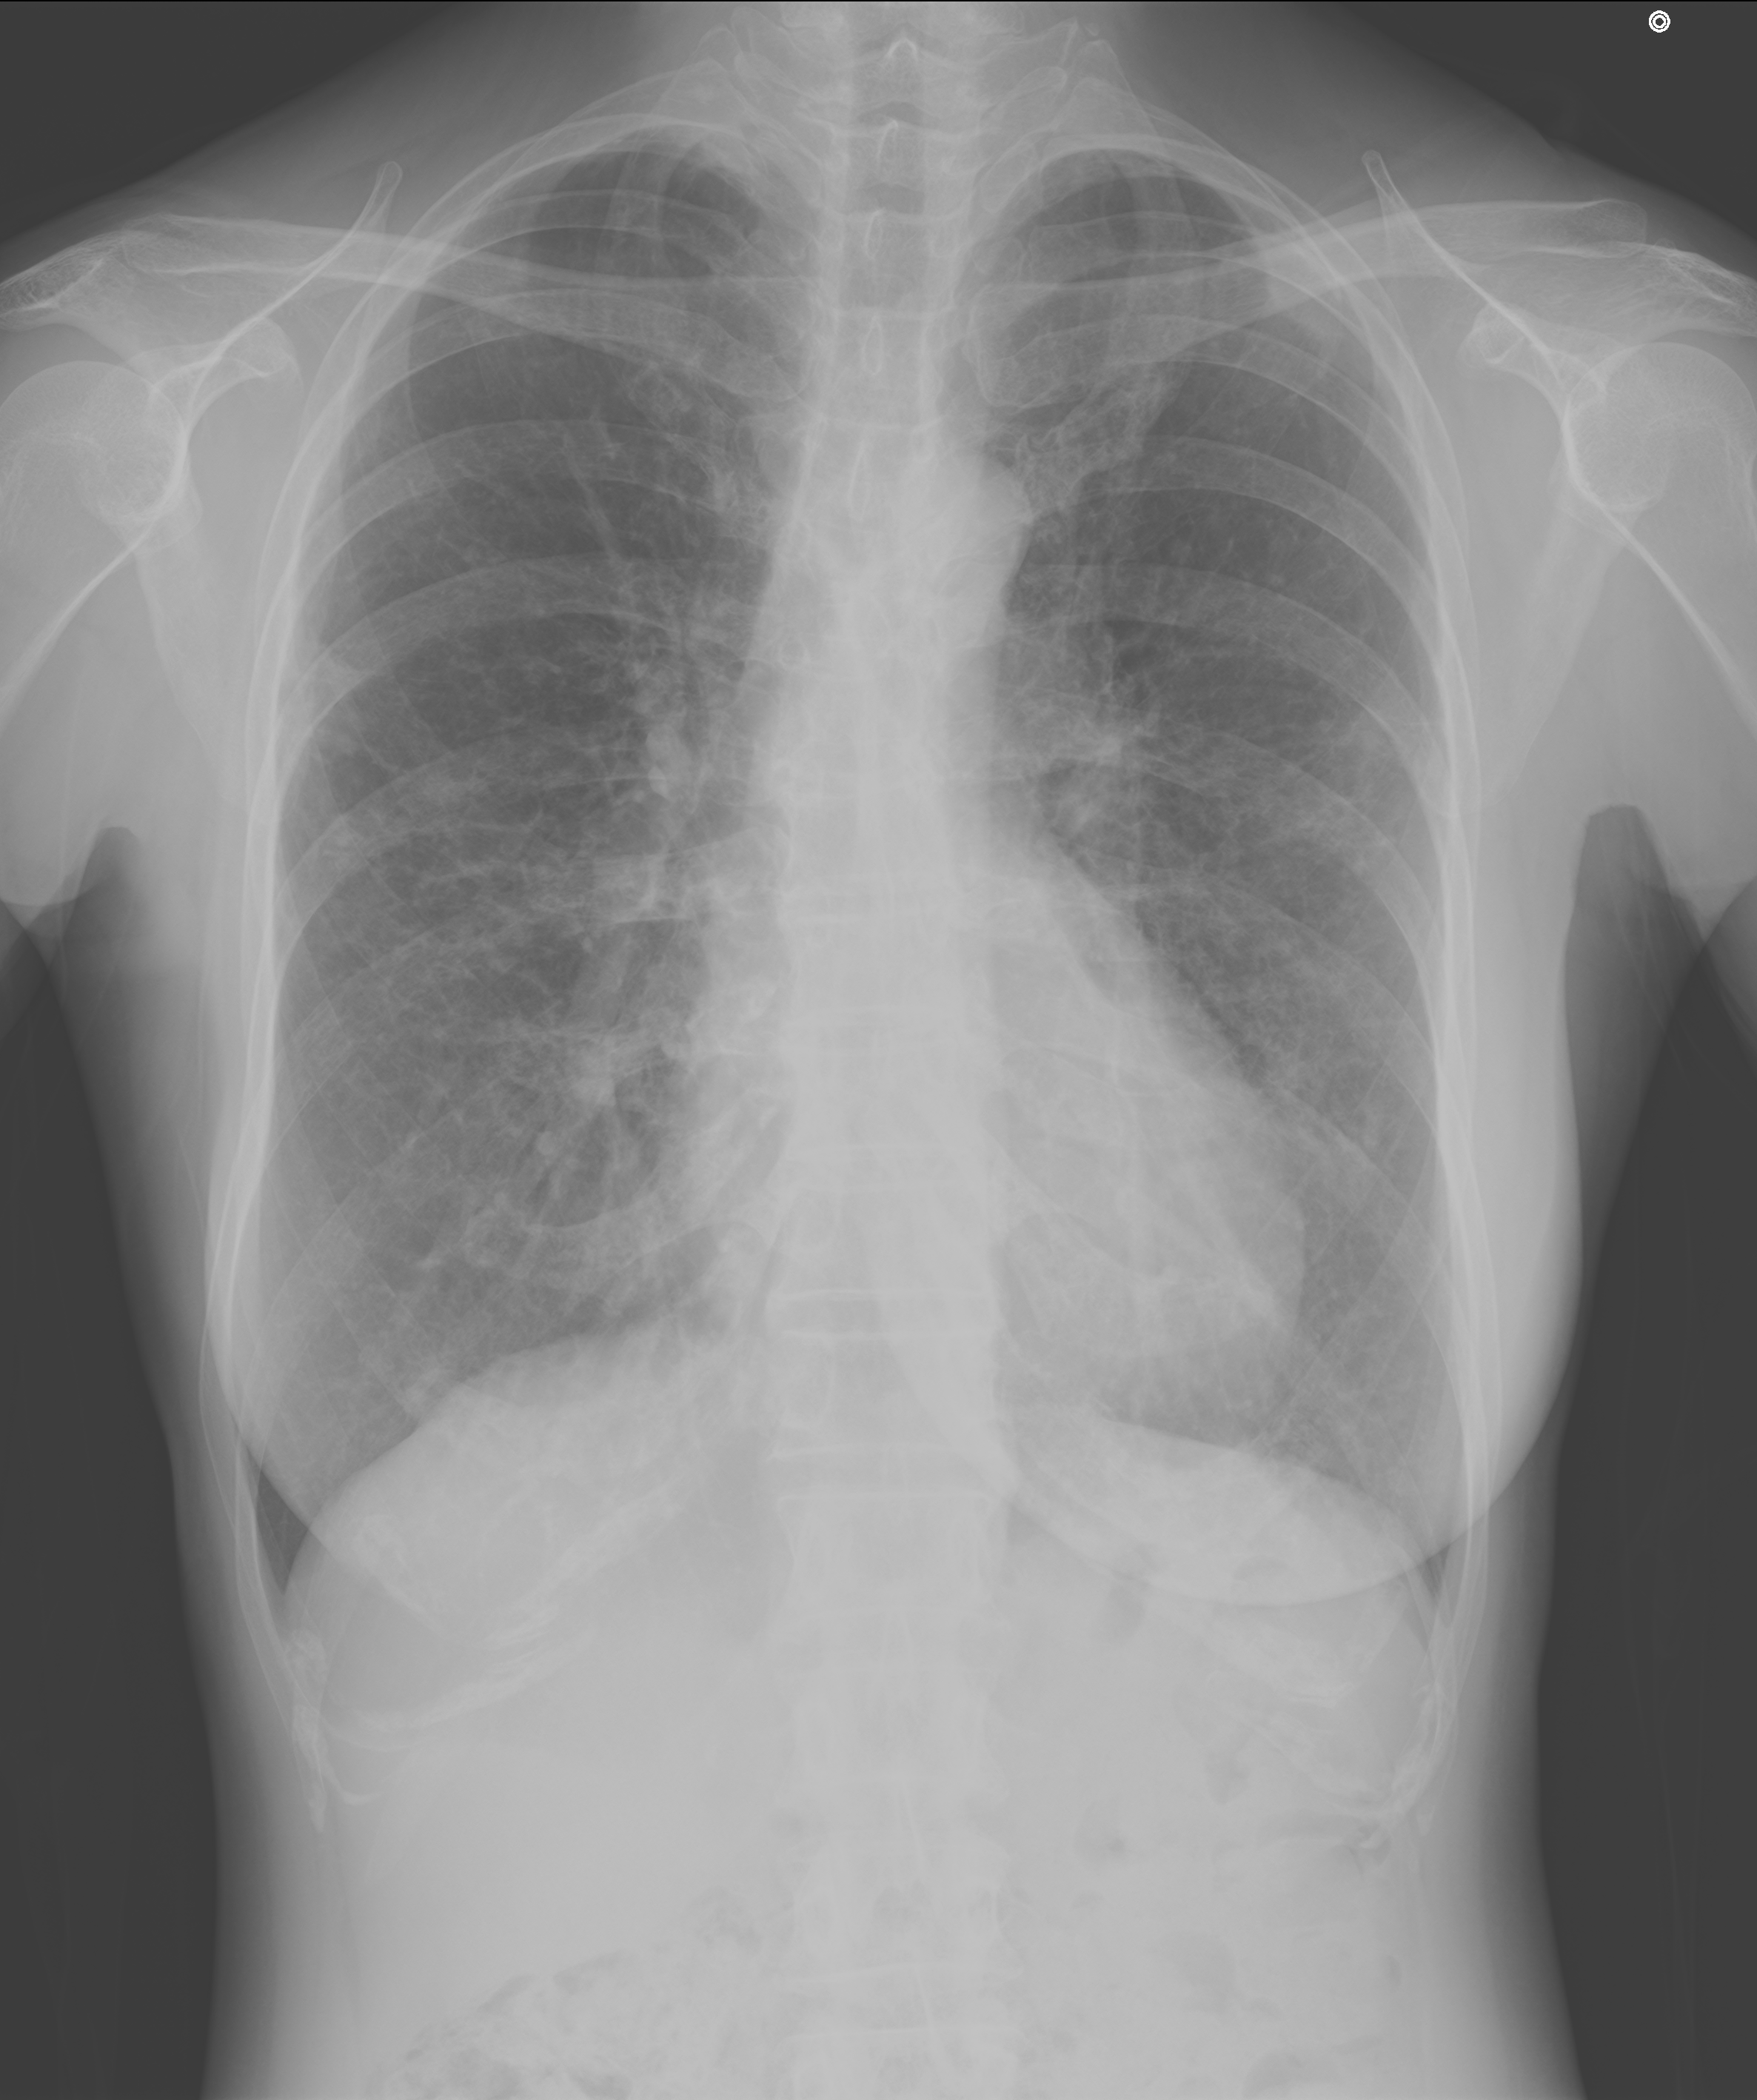

肺X線画像

- 2024.03.15 他病院での人間ドック時の画像